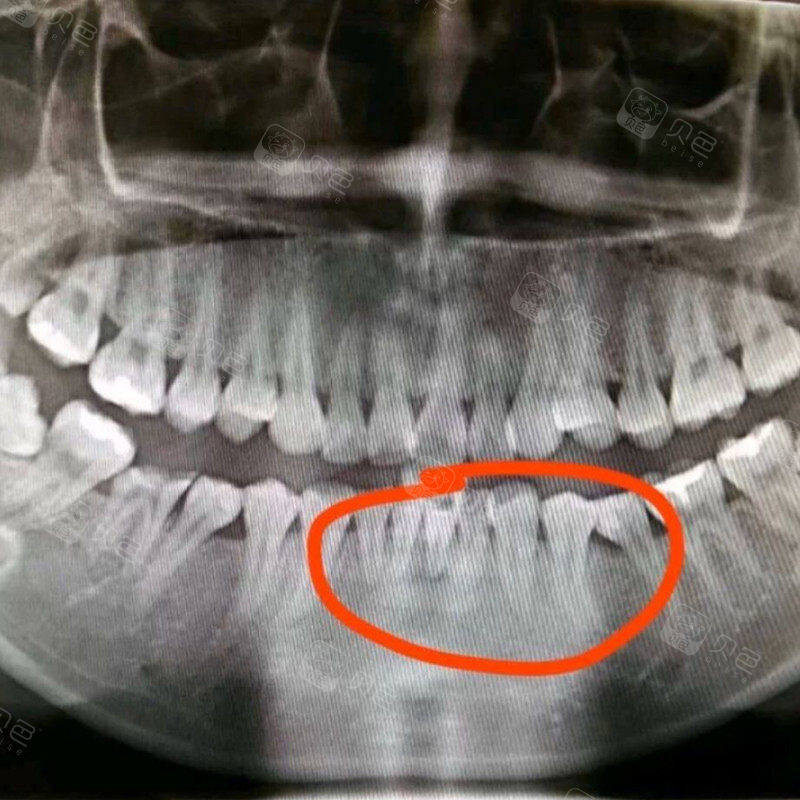

麻烦各位看一下牙根吸收严重吗?_牙齿矫正_金属矫正_美妆_医美整形